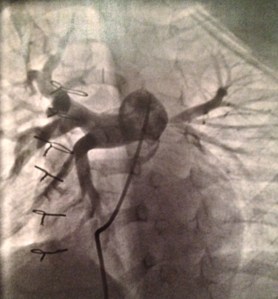

When I was matched with Cheng Chun (Iris), there was an added complication because I was not familiar with her specific congenital heart defect. My adoption agency gave me a list of specialists that regularly review medical files, and I also reached out to my local contacts. Over the next 72 hours, I had lengthy conversations with four doctors, and received opinions that teetered between unfavorable, and frightening. I had a huge pit in my stomach as I tried to process the severity of Cheng Chun’s condition, the complexity and risks of surgery, her long-term prognosis, and the impact to Solana. I had a few more phone calls to make, and next on my list was Dr. Mark Reller, head of cardiology at Doernbecher. I told Dr. Reller about the opinions I received, and my fears. Dr. Reller’s opinion was dramatically different from the others, and he optimistically said, “You need to call Dr. Stephen Langley. He has successfully performed this surgery with great outcomes.”

Dr. Langley and I connected less than an hour before I needed to give an answer to my adoption agency. Dr. Langley walked me through the surgery, recovery, short-term challenges, and long-term prognosis. His next statement is forever imprinted in my mind; “If you adopt this little girl and I perform her surgery, I will do everything in my medical power to give her the best chance for a long, healthy life.” I still can’t say, or write, those words without tearing up. I had only met Dr. Langley once briefly, but I was well aware of his reputation and integrity, and I knew he wouldn’t make that statement unless he was confident that he could fulfill it. So I believed him. With every part of my being .. I believed him.

On January 28th, 2013, Solana and I were united with Iris in Hefei, China. In the coming weeks I learned that Iris’ condition was even more serious because of the malformation of her trachea, but Dr. Langley had planted a seed of trust, and although I was scared, I knew Iris was in the best hands possible. On June 28th, 2013 the promise within Dr. Langley’s words was fulfilled as he and Dr. Michael Rutter (the amazing otolaryngologist from Cincinnati Children’s Hospital) worked side by side, seamlessly, to repair Iris’ heart and reconstruct her trachea.